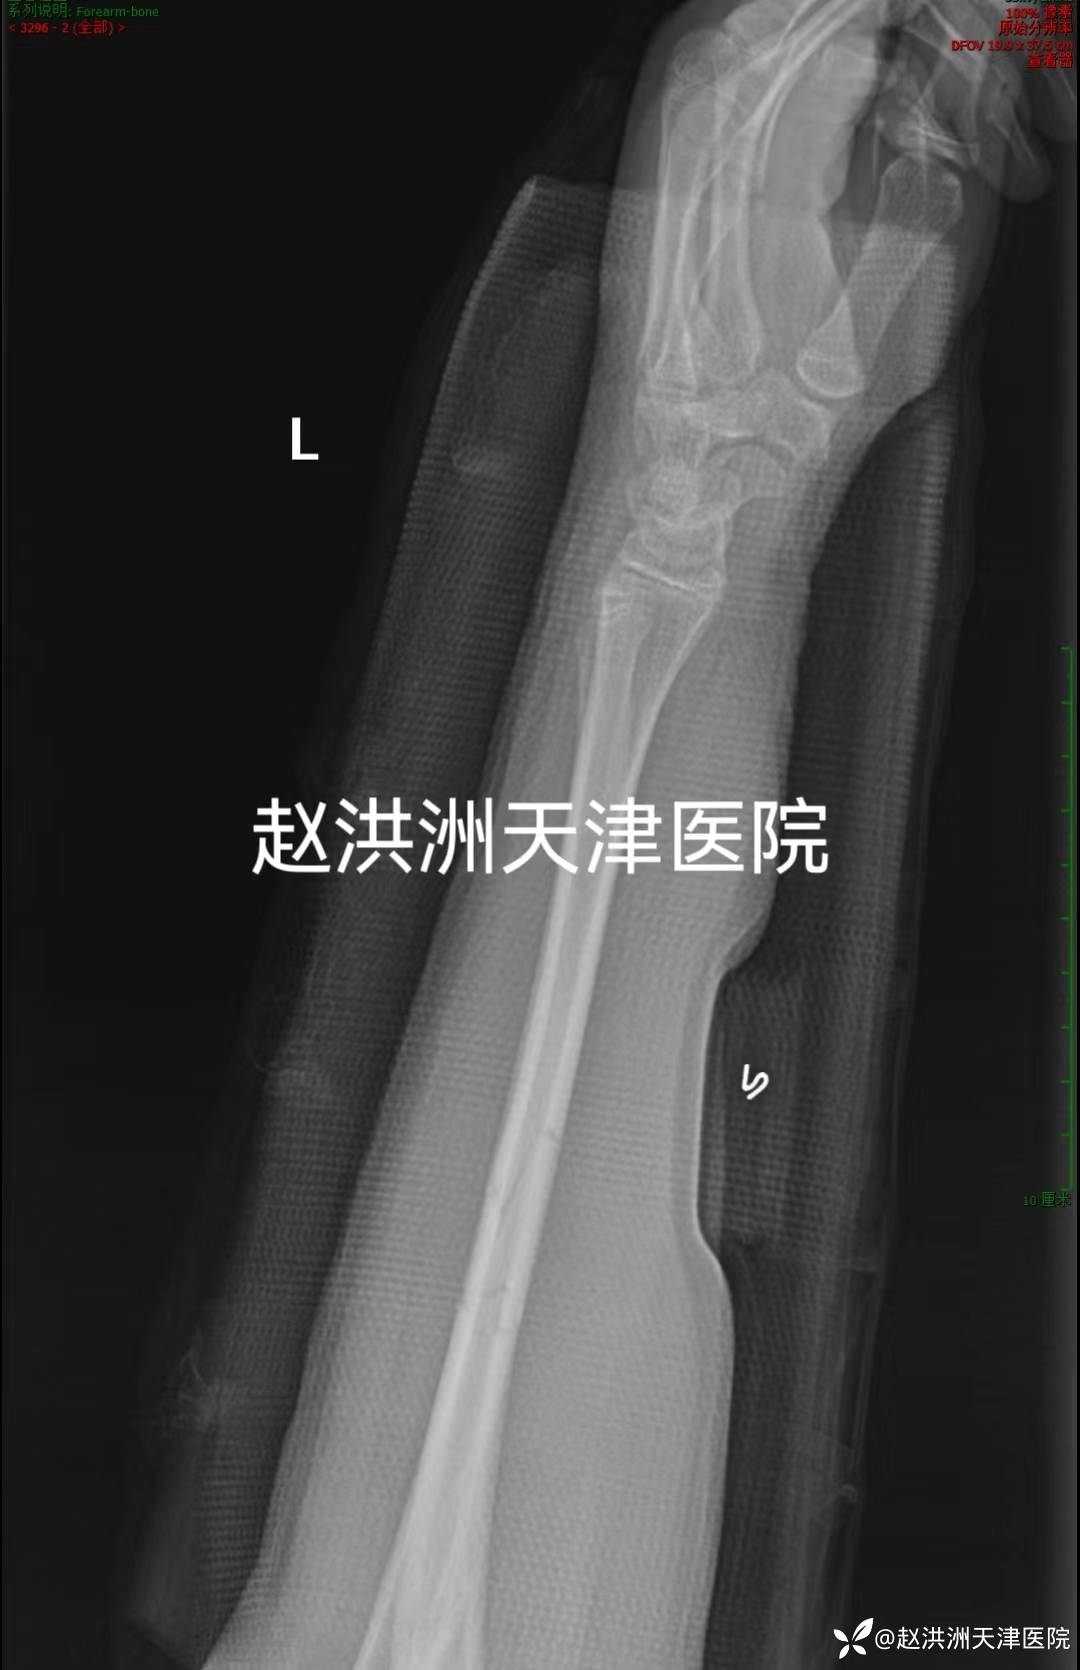

患者男性13岁摔伤致左前臂双骨折,来院就诊。

予天医“三点挤压”正骨手法复位,前臂夹板长上肢石膏托功能位外固定,复位后骨折解剖对位。